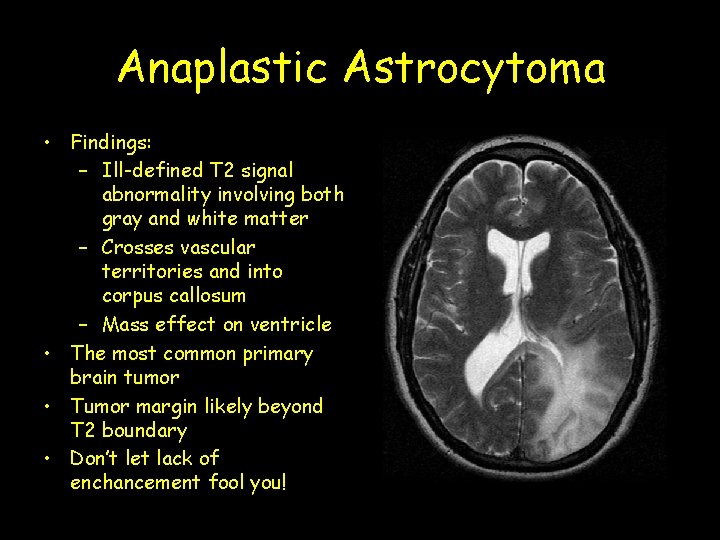

Anaplastic Astrocytoma • Findings: – Ill-defined T 2 signal abnormality involving both gray and white matter – Crosses vascular territories and into corpus callosum – Mass effect on ventricle • The most common primary brain tumor • Tumor margin likely beyond T 2 boundary • Don’t let lack of enchancement fool you!